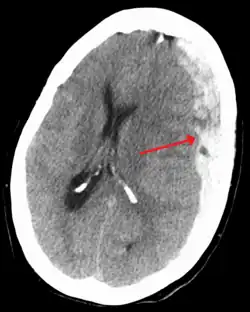

![]() Hematoma subdural (flecha), sangrado entre la duramadre de las meninges y el cerebro, se produce con frecuencia en SBS | ||

El síndrome del niño sacudido, también conocido como síndrome del niño zarandeado o agitado o síndrome del bebé sacudido (SBS) es una constelación de hallazgos médicos (a menudo designada como la "tríada"): hematoma subdural, hemorragia retinal, y edema cerebral, por la que los facultativos, de acuerdo con los conocimientos médicos actuales, deducen maltrato infantil causado por sacudidas violentas, sacudidas muy peligrosas debido a que el cerebro del bebé o niño pequeño aún no ocupa toda la caja craneal. En la mayoría de los casos no hay signos visibles de lesión externa. El síndrome del niño sacudido es un subconjunto de una forma de maltrato infantil más amplia llamada trauma cerebral abusivo o trauma cerebral por maltrato.[1] El CDC, Centers for Disease Control and Prevention, de los Estados Unidos, identifica SBS como "una lesión en el cráneo o contenidos intracraneales de un bebé o niño pequeño (< 5 años de edad) debido a un impacto contundente y/o sacudida violenta".[2]

Lesiones características asociadas con SBS incluyen hemorragia retinal, fracturas múltiples de los huesos largos, y hematomas subdurales (hemorragia cerebral).[8] Estas señales se han desarrollado con los años como las señales aceptadas y reconocidas de maltrato infantil y síndrome del bebé sacudido. Los profesionales médicos sospechan firmemente de sacudida como causa de lesiones cuando el bebé o niño pequeño presenta hemorragia retinal, fracturas, lesiones de tejidos blandos o hematoma subdural, que no pueden ser explicados por trauma accidental u otras afecciones médicas.[9]

El SBS puede ser mal diagnosticado o subdiagnosticado, y los cuidadores pueden mentir o no ser conscientes de los mecanismos de la lesión.[18] Normalmente, no hay signos visibles de la afección.[18] El examen de un oftalmólogo a menudo resulta fundamental en el diagnóstico de síndrome de bebé sacudido, ya que formas particulares de derrame ocular son muy características.[33] Imágenes por resonancia magnética también pueden mostrar sangrado retinal;[17] Puntualmente esto puede resultar útil si un examen del oftalmológo se retrasa o no está disponible.[cita requerida] Afecciones que deben ser descartadas incluyen hidrocefalia, síndrome de muerte súbita del lactante (SMLS), trastorno convulsivo, y enfermedades infecciosas o congénitas como meningitis y trastornos metabólicos.[19][34] Se utilizan exploración por TAC e imágenes por resonancia magnética para diagnosticar la afección.[18] Afecciones que pueden acompañar SBS incluyen fracturas óseas, lesión de la vértebras cervicales (en el cuello), hemorragia retinal, hemorragia cerebral o atrofia, hidrocefalia, y papiledema (hinchazón del disco óptico).[14]